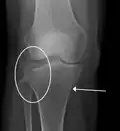

Fractura de meseta tibial leve en vista con Rayos X AP en la rodilla -

Una fractura de meseta tibial vista con rayos-X